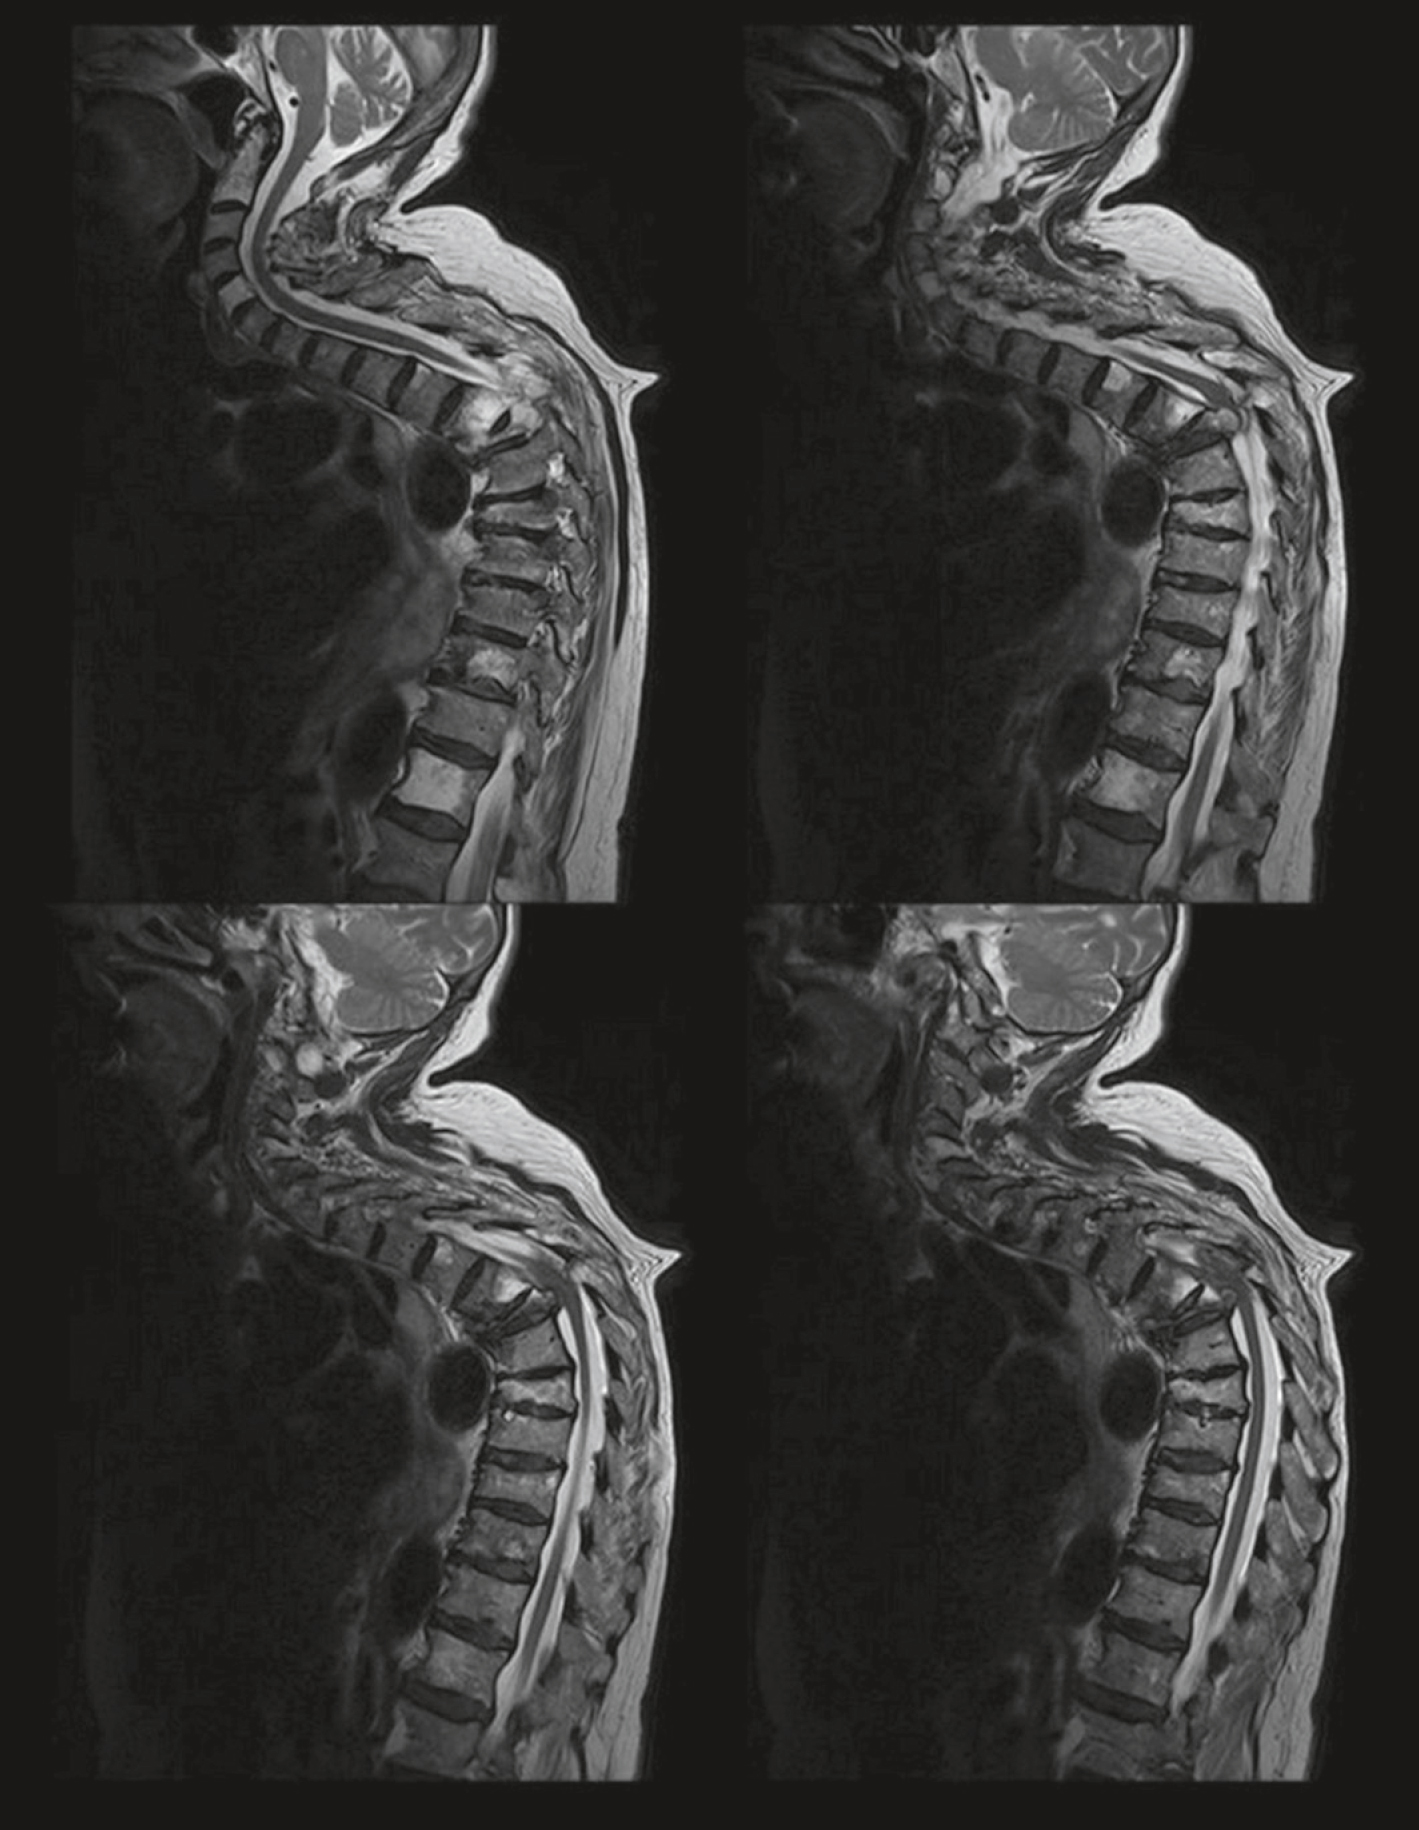

QRU 11

Un homme de 52 ans atteint d’un adénocarcinome bronchique se présente pour des douleurs dorsales associées à des troubles de la marche évoluant depuis 2 semaines. Vous réalisez l’IRM suivante (fig. 32.1) et suspectez une épidurite métastatique. Parmi les propositions suivantes, à quelle hauteur avez-vous la plus grande probabilité de retrouver un niveau lésionnel sensitif ?

Édition de quatre épines de la médullaire d'une coupe sagittale. Il a été généré à différents moments et séquences et a montré le cou et la moelle épinière. L'alignement vertébral est généralement respecté et il y a une bonne définition des vertèbres et des disques. Au niveau de la charnière thoracique cervicale dans une séquence particulière, il existe une membrane intramédullaire qui provoque une détresse médullaise ou un œdème local, vraisemblablement associée à une compression chronique. Aucune lésion osseuse destructrice n'est observée, mais la marque semble être soigneusement aplatie à son fond, ce qui peut correspondre au débutant-myéloïde. L'analyse comparative de ces séquences permet l'étendue et le type d'atteinte de la moelle épinière.

- A 671au niveau du cou

- B au niveau des mamelons

- C au niveau de l’appendice xyphoïde

- D au niveau de l’ombilic

- E au niveau des plis de l’aine